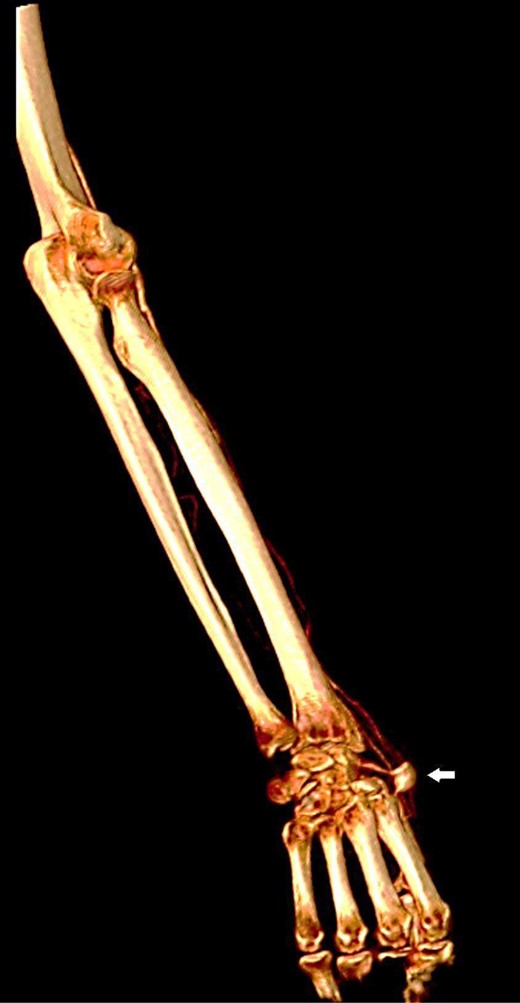

Reconstructed three-dimensional image shows radial artery saccular aneurysm (arrow).